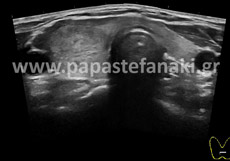

Υπερηχογράφημα Μαστών

Το υπερηχογράφημα μαστών αποτελεί μία από τις εξετάσεις διερεύνησης της παθολογίας του μαστού

Προετοιμασία ασθενούς Δεν απαιτείται.

Πρέπει να προσκομίσετε προηγούμενη μαστογραφία ή/και υπερήχους μαστών.